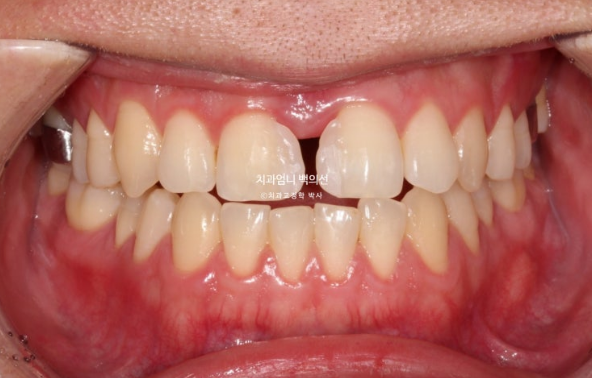

This is what it looked like in January 2023, one month after the initial visit, with the expansion device in place.

The palatal expansion device installed in the palate is not visible from the front.

Expansion began in January 2023, and in February, although the suture had not yet opened, the expansion device could no longer turn. A minor procedure called corticopuncture was performed to actively promote separation of the palatal suture.

After that, expansion was successful in March, creating a large space between the front teeth.